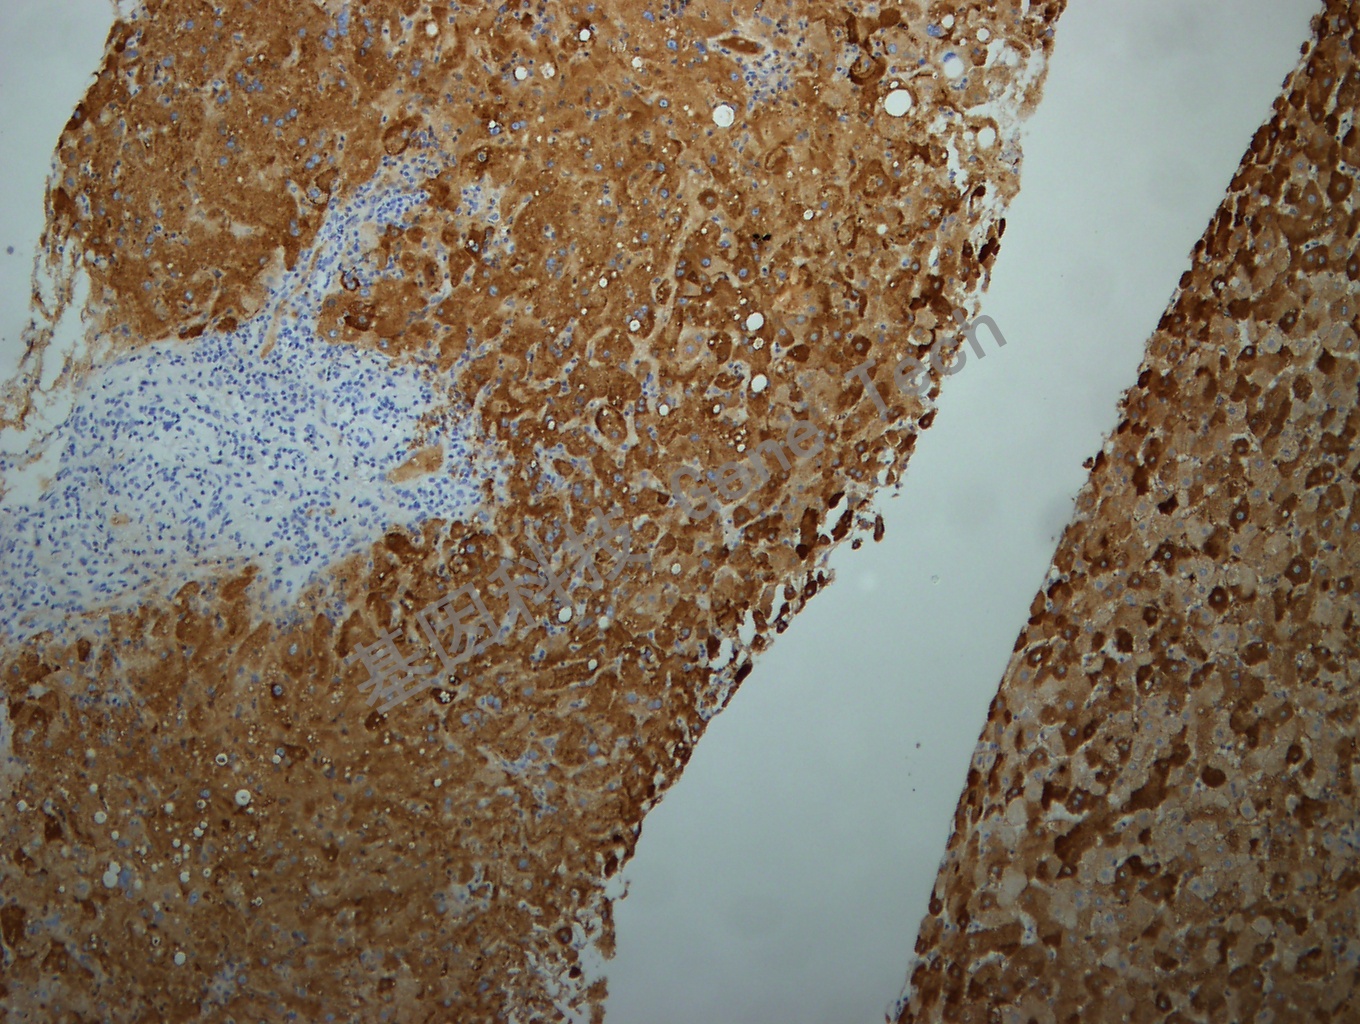

HBsAg 鼠抗人 乙型肝炎病毒表面抗原(HBsAg) 抗體試劑(免疫組織化學法)

| 預處理:高pH熱修復 | 陽性部位:細胞漿 | 陽性對照:HBV感染的肝組織 |

| 簡介:HBsAg(Hepatitis B surface antigen, 乙型肝炎表面抗原)是乙型肝炎病毒感染的標志物之一。在感染組織的細胞漿中呈現(xiàn)彌漫性著色,主要用于研究乙肝病毒表面抗原感染的組織,也可用于肝硬化、肝癌與乙肝病毒感染的相關性等方面研究。 | ||

| 乙肝石蠟切片,用 HBsAg(GT2224)染色,細胞漿陽性,DAB 顯色。 | ||